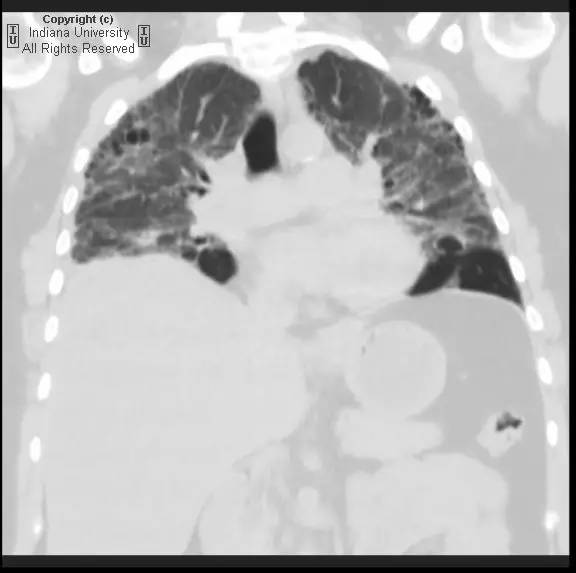

【影像学表现】胸片示双肺纹理增多,间质性透光度减低。无局灶性病变,气胸或胸腔积液。心脏及纵膈轮廓正常。CT示双肺弥漫间质性病变,累及所有肺叶,以下叶为著。肺间质增厚,结构扭曲,牵拉性支气管扩张,外周呈蜂窝状改变。肺动脉增粗,符合肺动脉高压。

【诊断】普通型间质性肺炎/特发性肺间质纤维化(活检证实)

Usual interstitialpneumonia / idiopathic pulmonary fibrosis (biopsy proven).